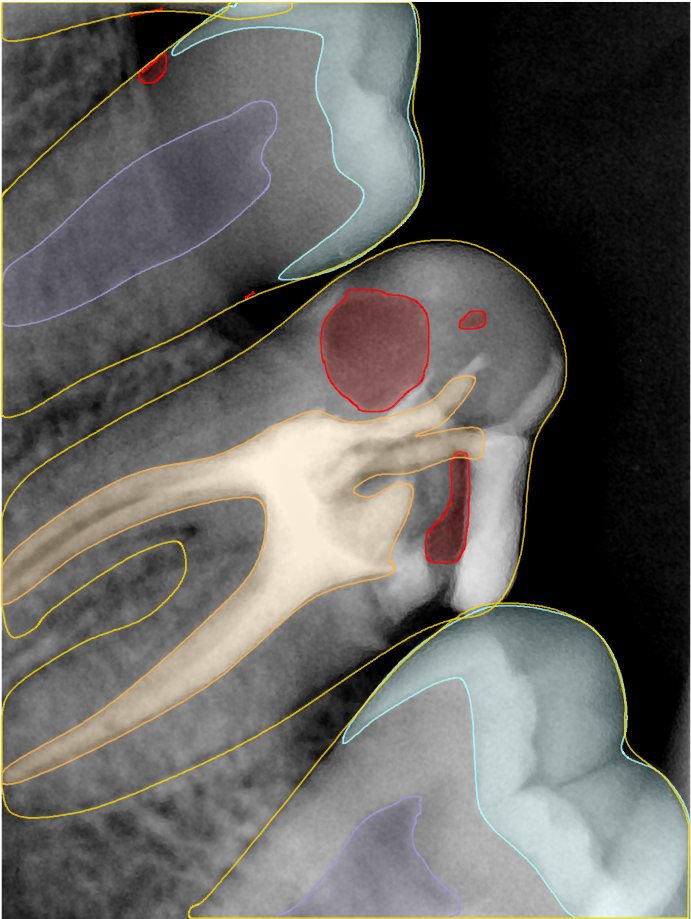

CR/DR 牙齿分割阶段记录

当前进展

- 完成了 CR/DR 牙齿相关分割训练

- 当前结果已经达到阶段预期,但仍有细节问题需要继续处理

相关测试

遇到的问题

- 训练过程中出现过 mask 下移问题

- 部分结果会出现 box 填充异常

- mask 边缘仍然有比较明显的锯齿感

参考

第二版算法问题测试

Updated: 2026-04-13(更新日期)

| 第一版 | 第二版 | 是否解决 | |

|---|---|---|---|

![]() | ![]() ![]() 边角识别有问题 龋齿识别不全 牙髓识别不全 | ![]() | 解决 |

![]() | ![]() 边角识别有问题 识别信息有误 自查(牙冠识别不全) | ![]() | 解决 |

![]() | ![]() ![]() 边角识别有误 大范围填充识别遗漏 | ![]() | 解决 |

![]() | ![]() 识别信息不全 | ![]() | 解决 |

![]() | ![]() ![]() 边角问题 牙胶识别不全 牙冠识别不全 | ![]() | 解决 |

![]() 换图片 | ![]() | ![]() 牙冠部分稍微白了一些就识别成小范围修补,部分判断异常 | 部分解决,修复类略敏感,牙冠部分稍微白了一些就识别成小范围修补,部分判断异常。 |

![]() | ![]() ![]() 牙冠识别不全 牙髓不全 根尖炎龋齿识别有误 | ![]() | 解决 |

![]() | ![]() | ![]() | 解决 |

![]() 换图片 | ![]() | ![]() | 解决 |

![]() | ![]() 牙冠识别有误 | ![]() | 解决 |

![]() 换图片 | ![]() ![]() 边角识别有误 | ![]() 修复类敏感 | 部分解决,图像过白,导致修复类判断异常。 |

![]() 换图片 | ![]() 牙冠识别不全 | ![]() 修复类敏感 | 部分解决,图像过白,导致修复类判断异常 |

结论:修复类出现了不鲁棒的情况,后续需要加入轮廓的扩充数据进行增强。